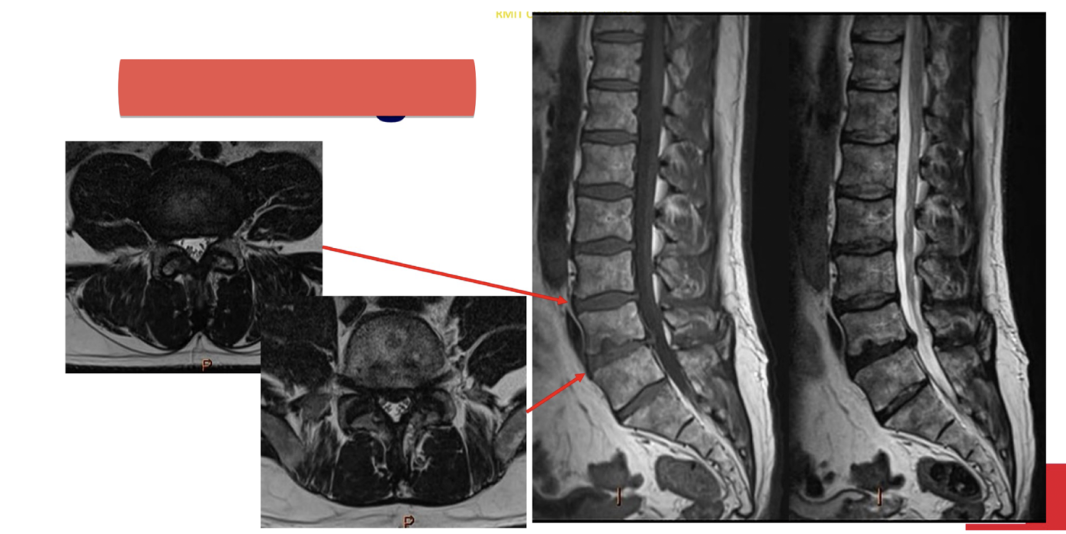

Sequence + Pathology?

T1,T2

• Cauda Equina syndrome

• L5/S1 disk space herniation compressing the cauda equina.

• Signal intensity is lost in T2 sag as you get to L5/S1 disk space.

Sequences + pathology?

• Axial=T2,1st sag=T1,2nd sag=T2

• Anterior disk bulge of L3/4 and L4/5 disks

• Anterior longitudinal ligament has lost its normal shape as it is being pushed

anteriorly by the disk bulges.